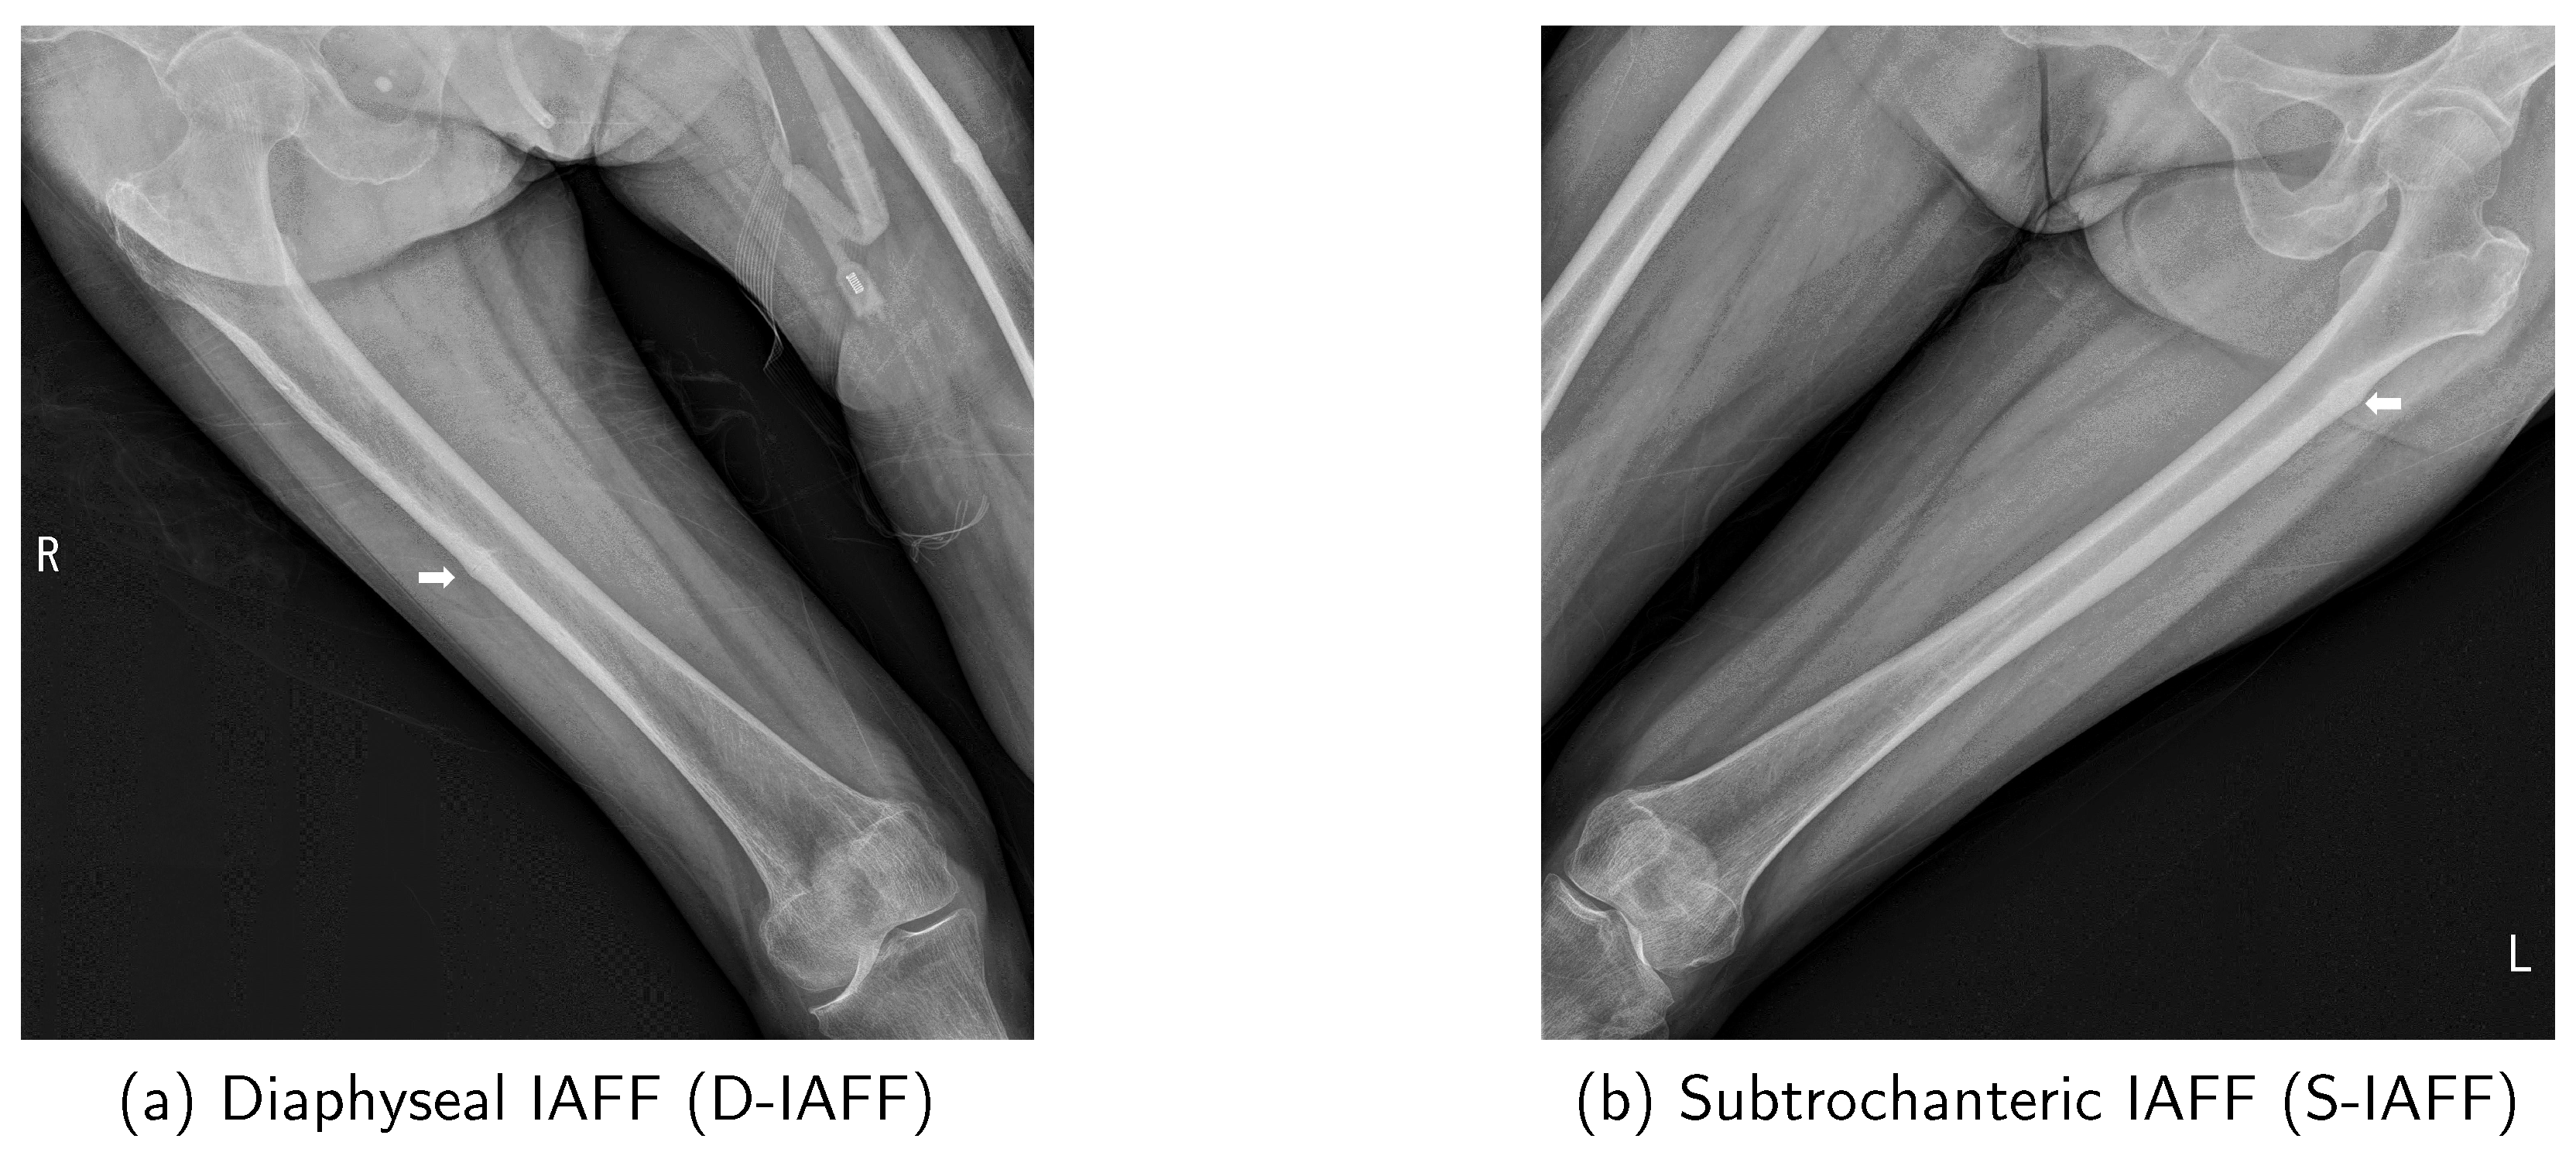

In the early stages preceding the occurrence of AFF, cortical buckling will develop in the lateral cortex of the femur due to repeated cycles of microfracture and healing [12]. This condition is termed Incomplete Atypical Femoral Fracture (IAFF). IAFF exhibits various characteristics and is classified based on its location as shown in Figure 1: Diaphyseal IAFF (D-IAFF), which occurs in the femoral shaft, and Subtrochanteric IAFF (S-IAFF), which occurs in the subtrochanteric region [13]. Although IAFF is a crucial precursor to AFF, it is often asymptomatic or presents with vague features, making detection difficult and often resulting in delayed diagnosis. As a precursor to AFF, the progression process from IAFF to AFF is illustrated in Figure 2. IAFF is typically diagnosed through bone scans [14] or Magnetic Resonance Imaging (MRI) [15]. However, these diagnostic methods have notable drawbacks, including high costs and time consumption. Furthermore, there remains the risk of misdiagnosis [14], which can lead to either unnecessary or delayed interventions, ultimately culminating in a complete fracture.

To mitigate these problems, the development of a diagnostic support system utilizing X-rays is essential, but there are several obstacles to be overcome: (1) An IAFF is often extremely small in size, (2) lacks distinct characteristics, and (3) is similar to normal anatomical deformations, making it easy to overlook. Additionally, (4) the location and features of an IAFF vary depending on the type, and (5) its appearance may differ slightly depending on the radiographic view, even for the same patient (Figure 3). Due to these factors, even experienced orthopedic specialists may miss an IAFF if they do not examine it meticulously.